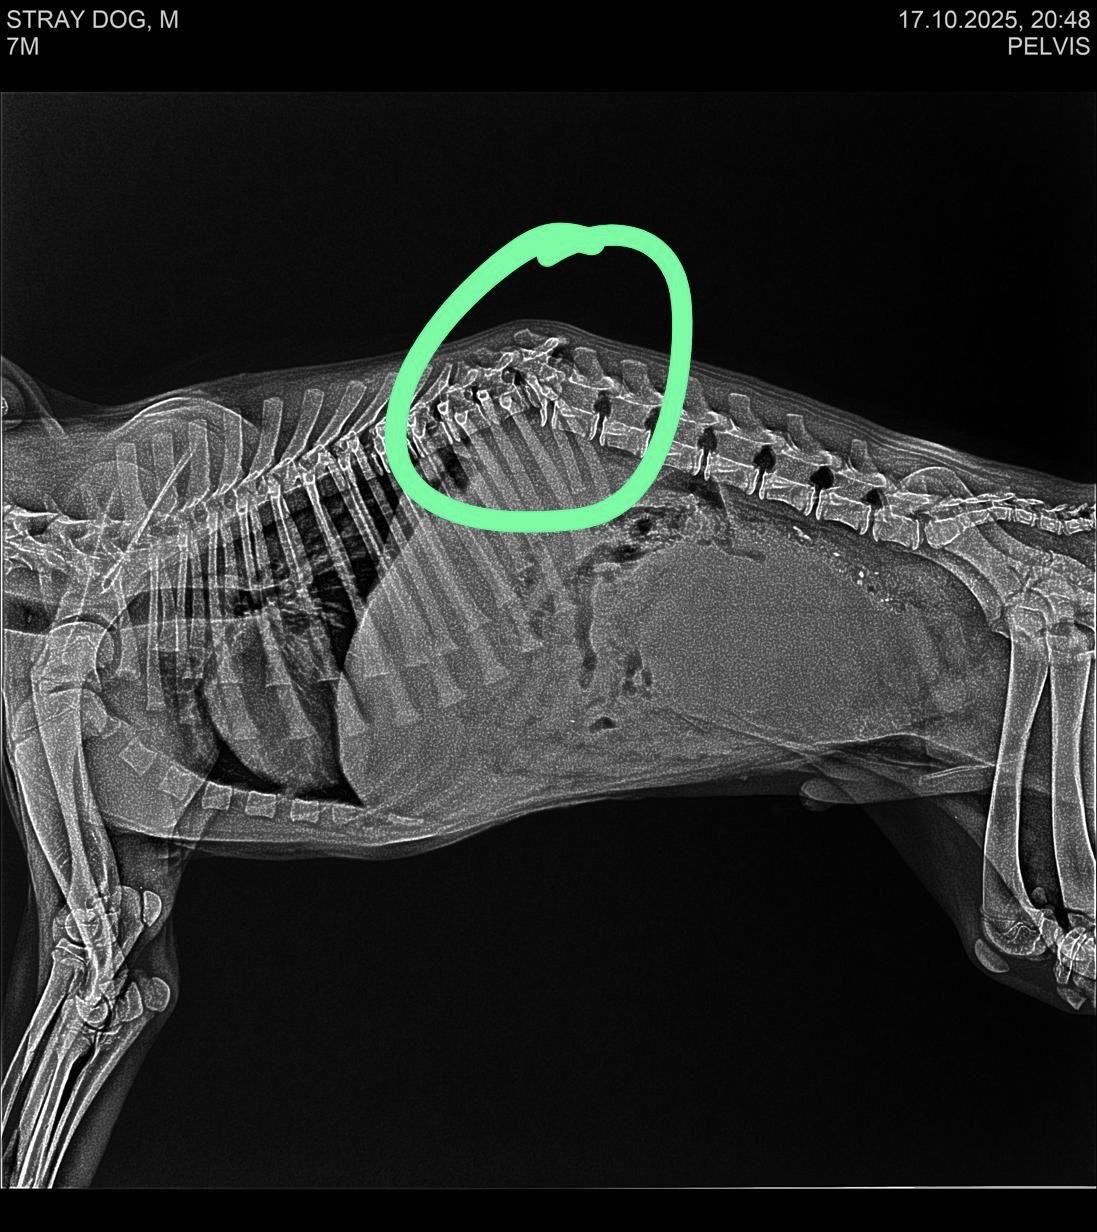

Tommy was found lying completely still by the roadside, unable to move his hind legs. Local residents contacted a nearby NGO, who took him for X-rays that revealed a spinal fracture. He needed immediate specialist care, but the NGO was short on resources. Late that night, they reached out to us, and Tommy was brought to our centre.

The next morning, we rushed him to Bangalore for a CT scan. The results gave us hope — his spinal cord isn't completely damaged. He could recover. He could walk again. But only with immediate spinal surgery.